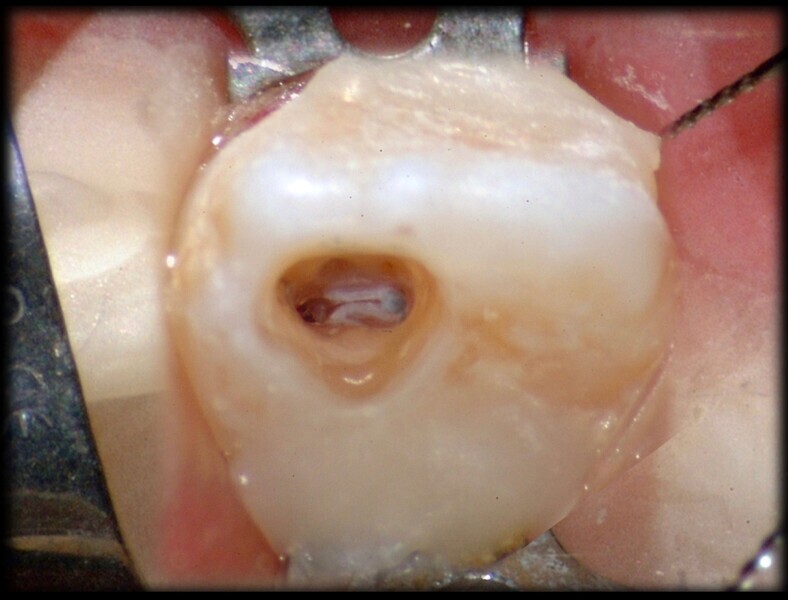

Use of 3D technology in the diagnosis and treatment of endodontic disease